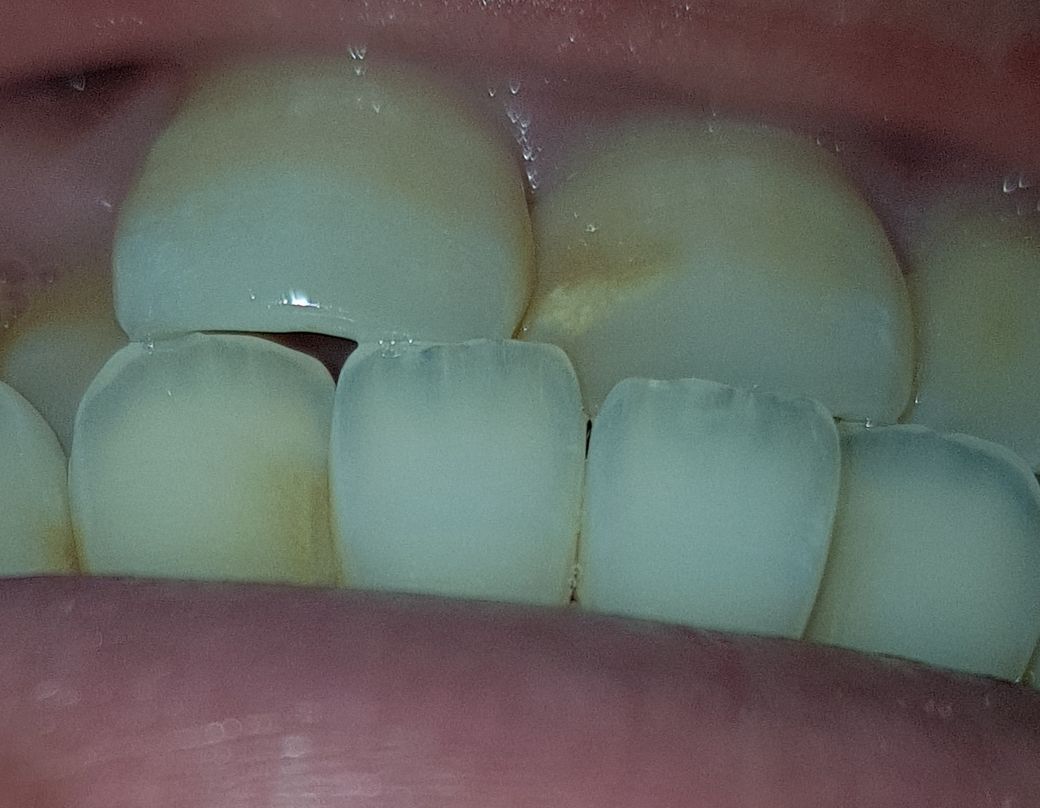

이번주 토요일날 치과가는데 충치인건가요?

충치가 맞는건가요??

1년만에 충치가 진행되기도 합니다..앞니는 치아탈회로 보이며 완성된 형태의 충치가 아니므로 잘 관리하면 충치로 진행을 막을수 있습니다.

현재 사진만으로는 정확한 판단이 어려워 보입니다. 방사선 사진까지의 자료가 필요합니다. 다만 1년이라는 시간이 지나면 충치가 생길 가능성이 충분히 있으므로 갑자기 진행되는 경우도 많습니다.

사진상으로는 크게 충치가 잇어 보이진 않지만, 위 앞이 바깥쪽은 치아가 선천적으로 약하게 태어난거 같으니 관리를 잘해주시는게 좋을것같습니다.